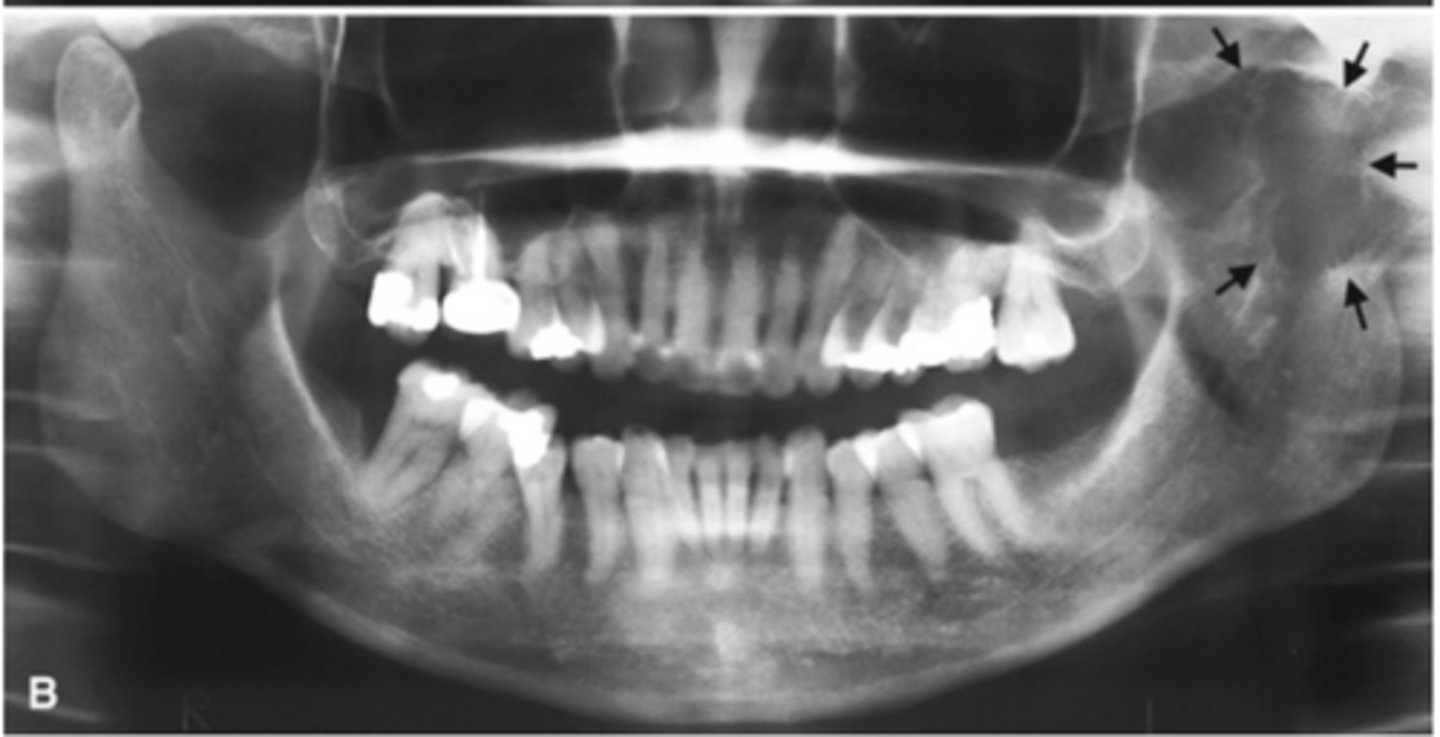

Patient has DJD.

The top images show the subchondral/ Ely cyst, a pseudocyst of connective tissue, granular tissue and osteoid, the bottom images show the same patients left side with broad erosion, a lack of cortication, loss of joint space.

What is the diagnosis of the patient based off these radiographs and what are the features? (Top images = patients right condyle) (bottom images= same patients left condyle)